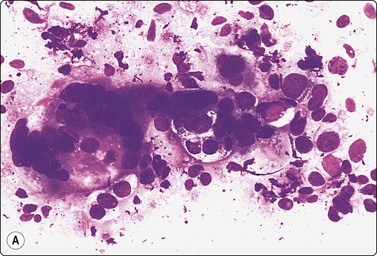

Embryonal carcinoma (Figs 13.33 and 13.34)14,58-61,63,65,66

image image

Fig. 13.33 Embryonal carcinoma

(A) Adenocarcinoma-like tissue fragment of large malignant cells with large vesicular nuclei, coarse chromatin, prominent nucleoli; prominent cytoplasmic vacuolation (MGG, HP); (B) Fragment of undifferentiated mesenchymal tissue right; cluster of malignant epithelial cells with large vesicular nuclei and prominent large nucleoli (H&E, HP) left.

image

Fig.13.34 Embryonal carcinoma

Tissue section corresponding to Fig. 13.33B (H&E, IP).

Criteria for diagnosis

Cell-rich smears,

Frequent three-dimensional clusters,

Occasional tendency to acinar and microglandular grouping,

Large vesicular, obviously malignant nuclei, large nucleoli,

Indistinct cell borders,

Basophilic to amphophilic, sometimes pale, vacuolated cytoplasm,

Immunocytochemistry: cells positive for PLAP, OCT 3/4, CD30, AE1/AE3 and CK7.

The vesicular nuclei of embryonal carcinoma are larger and more pleomorphic than those of seminoma, the chromatin is coarse and irregular and nucleoli are large, occasionally huge, and eosinophilic. The cytoplasm is pale and distinctly vacuolated, but not ‘bubbly’. It is not highly fragile and a TB as in seminoma is not seen. Cytoplasmic boundaries are poorly defined (Fig. 13.33). Hemorrhage and tumor necrosis may be prominent and may hamper the identification of diagnostic cells. It is usually not seen in smears of seminoma. Chromatin threads and reticulated material resembling TB can occur. Large syncytiotrophoblastic cells may be found. Prominent lymphoid/plasma cell infiltrates or mucus are not seen. The presence of cellular mesenchyme on its own does not warrant a designation of teratoma (Figs. 13.33B and 13.34).49